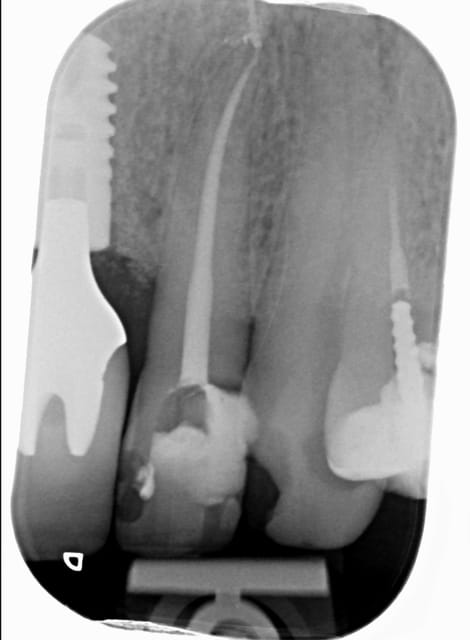

chicot29

Moi capteur rvg, ca me suffit largement. La manipulation des plaques est éliminatoire pour moi.

Pas suffisamment fin pour détecter cette fêlure sur cette 26 qui sera à extraire ( infection, pas de vitalité) mais une radio argentique n'aurait pas fait mieux. -)